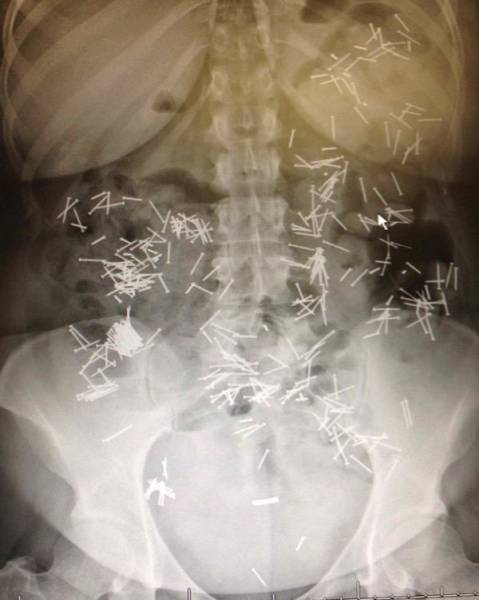

On suorastaan käsittämätöntä katsoa millaisia esineitä ihmiset nielevät ja tunkevat alapään kautta sisään. Röntgenosastolla työskentelevillä lääkäreillä on varmasti aika ajoin naurussa pidättelemistä, kun he löytävät alapäästä viinipulloja, kesäkurpitsoja ja jopa munakoisoja! Ihmiset ovat todella erikoisia varsinkin silloin, kun he yrittävät tyydyttää halunsa. Mukana on myös kuvia tapauksista, jotka sattuivat täysin vahingossa.#1 Naisen vatsasta löytyi 78 ruokailuvälinettä

#14 Nauloja???